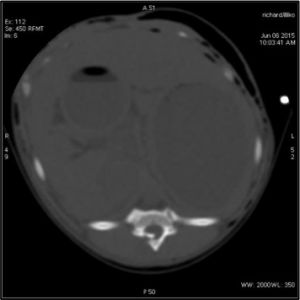

Un examen scanner de la région T3 L3 est réalisé ainsi qu’un corps entier afin d’évaluer toutes les lésions.

Images montrant la fracture de l’arc vertébral de T12, responsable de la parésie des postérieurs